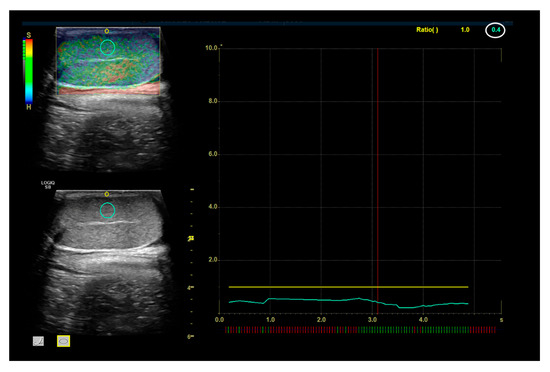

2.1.2. SE and 2D SWE Examination

3.2. Strain Elastography Evaluation